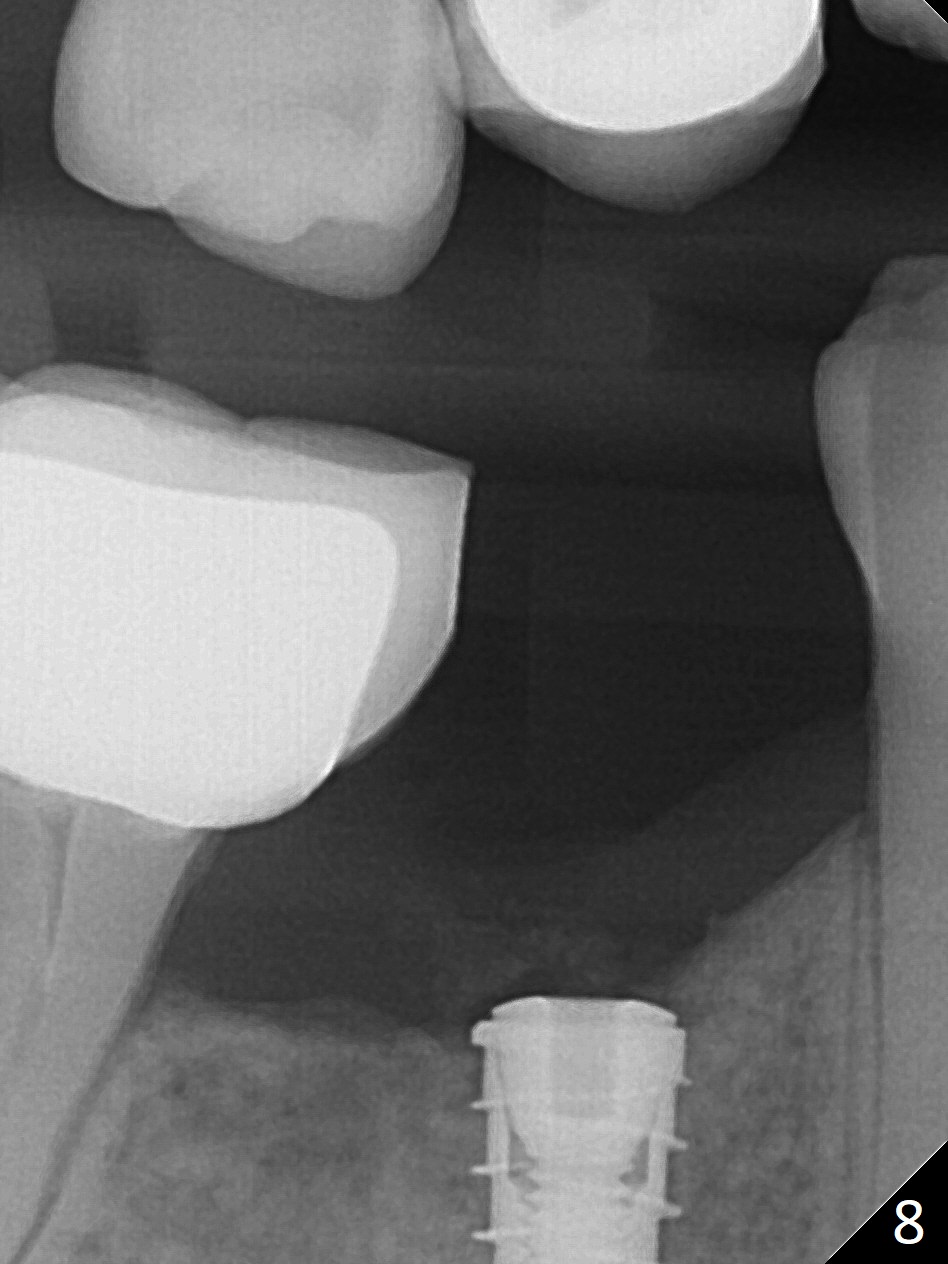

The patient returns for implant placement 11 months post extraction of #28 and 29. With flapless manner, initial osteotomy happens to drop into the original socket of #28 (Fig.4). After use of 3.3 mm Magic Drill (MD) and Final Drill for 15 mm, a 4x11 mm dummy implant is placed (Fig.5). It appears that the implant is long for the site (red dashed line: Mental Loop). However, a definitive implant (4x9 mm, IBS) has difficulty to reach its depth (Fig.6). After several rounds of untorque and retorque, the implant does not seat completely (Fig.7, implant driver disengagement) with autogenous bone placed distal (>). Retrospectively, a larger MD should have been used (3.8 mm) for complete seating in the dense bone. In fact she is post breast cancer treatment with 50% chance of relapse. The patient returns for follow up 1.5 months postop (Fig.8). The wound has healed. Impression is taken 5 months postop (Fig.9). When the crown is cemented, food impaction is an issue between the implant crown and crown at #30. Since the tooth #30 is mesially tilted with distal open margin and apical infection, the tooth will be extracted. Osteotomy is going to be initiated in the mesial slope of the mesial socket (Fig.9 red line). An implant will be placed more or less in the mesial socket (green box).